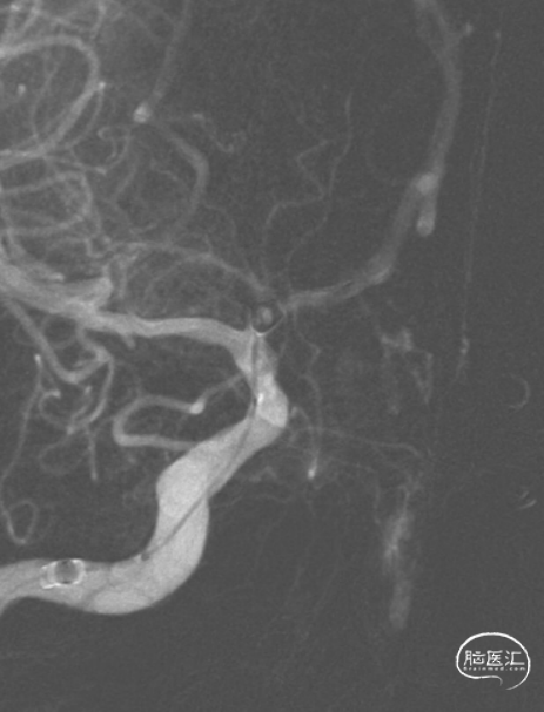

影像学检查:

2024年03月27日在局麻下行DSA检查。

右侧颈内动脉造影

左侧颈内动脉造影

1.该患者动脉瘤虽然是未破裂动脉瘤,动脉瘤不大;但动脉瘤为多发,且形态不规则,存在破裂出血风险,故建议患者积极处理。

2.对于A1起始部动脉瘤的介入治疗,栓塞微导管从同侧颈内动脉入路,微导管塑形较困难,而且手术过程中微导管到位困难以及稳定性也差;栓塞微导管从对侧到位是一个好选择,但术前评估A1与动脉瘤关系非常重要。

3.该患者双侧动脉瘤的栓塞微导管均是从对侧入路到位,也就是“左右开弓”;该患者双侧股动脉置鞘,栓塞微导管从对侧颈内动脉经前交通动脉到达对侧A1动脉瘤,行程路径长,所以每一步操作要谨慎,术中出现了载瘤动脉急性闭塞并发症,术者快速判断及果断处理非常重要,也就是“步步为营”;最终手术顺利完成,患者术后恢复良好,包括术后半年复查动脉瘤栓塞满意,终获“左右逢源”。